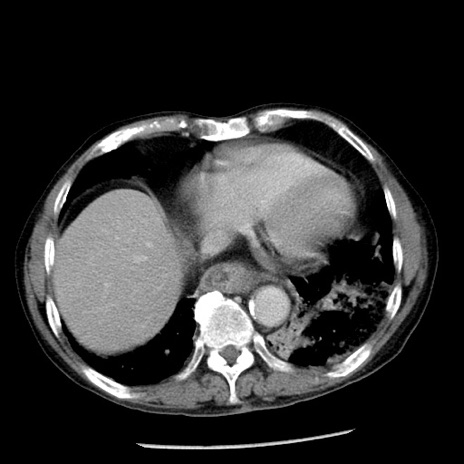

症例26(横断像)

【症例】80歳代男性

【主訴】嘔吐

【現病歴】昨晩2回嘔吐あり、今朝になっても嘔吐あり。来院。

【既往歴】胃潰瘍

【身体所見】意識清明、BT 37.6℃、BP 166/95mmHg、HR 100bpm、SpO2 97%、腹部:平坦・軟、腸蠕動音聴取良好、圧痛なし。

【データ】WBC 21900、CRP 1.46

冠状断像